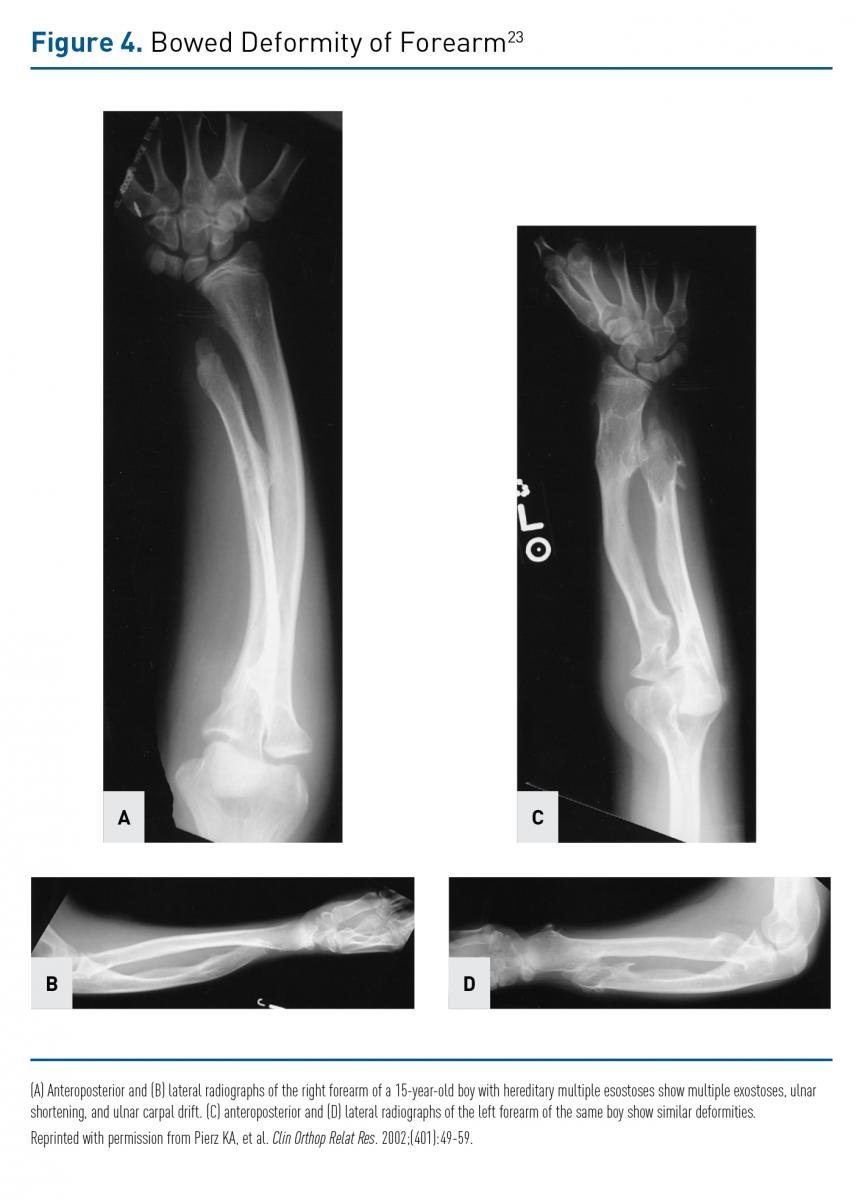

The MO osteochondroma usually presents as a thickened metaphysis with overlying cartilage (